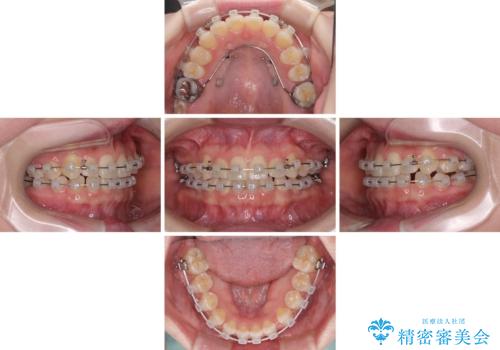

- クリアブラケット

- 1年3ヶ月

- 10-30回

- 八重歯を気にして来院された患者様です。

口腔内の状況を確認したところ、左右ともに下顎第二大臼歯が欠損しており、咬み合うべき上顎の第二大臼歯が著しく挺出していました。

挺出した大臼歯を元の位置に戻すことは現実的に難しいため抜歯することとし、補助装置とワイヤー装置により上顎歯列全体を後方に移動することとしました。